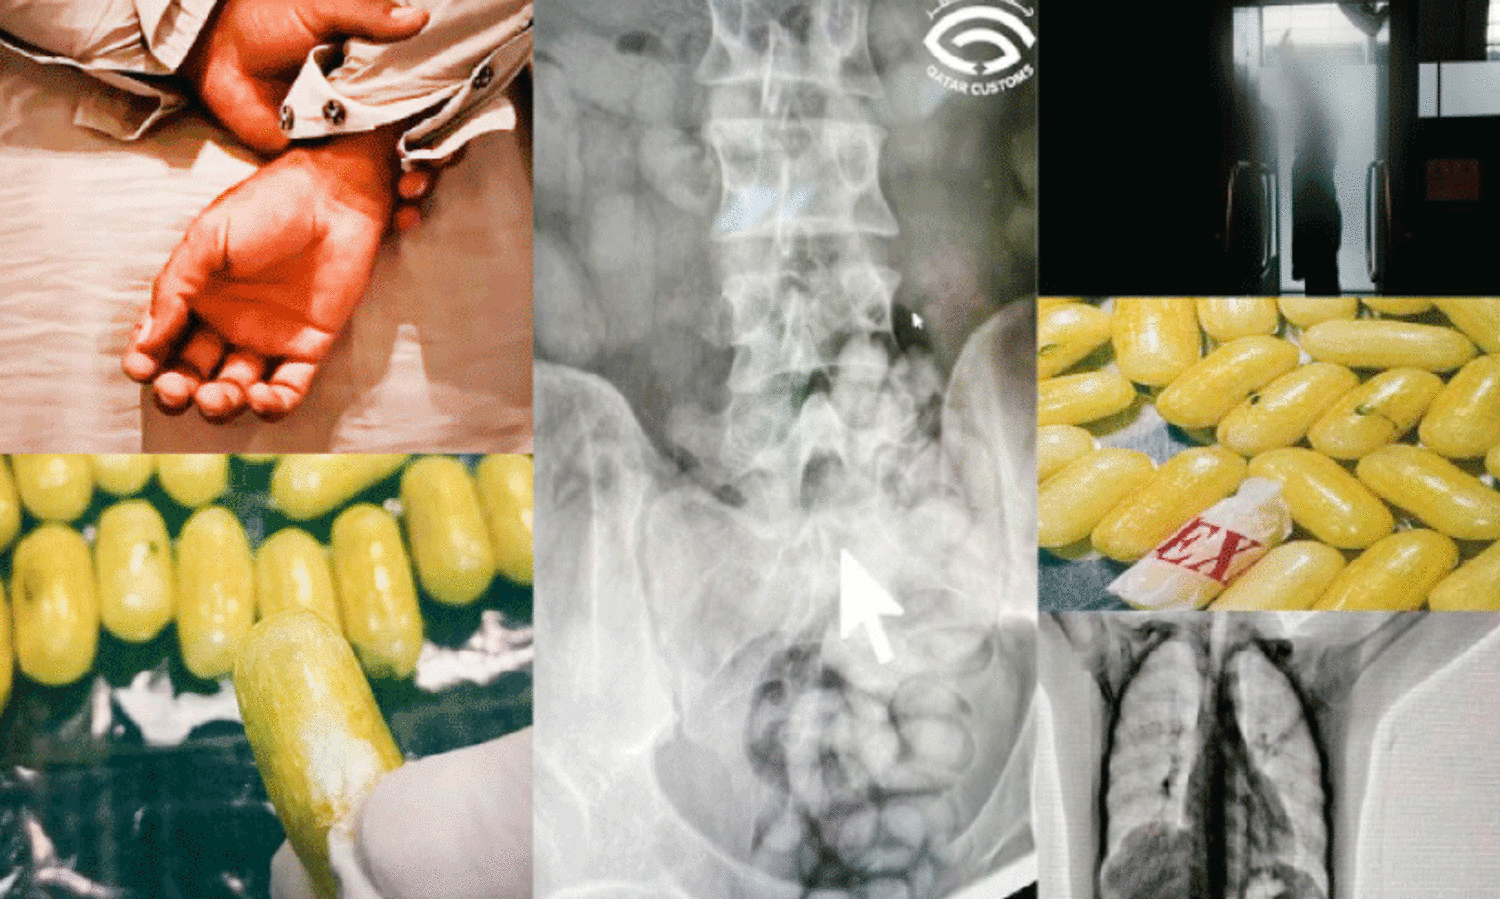

ലഹരിമരുന്ന് വിഴുങ്ങിയെത്തിയ യാത്രക്കാരൻ പിടിയിൽ